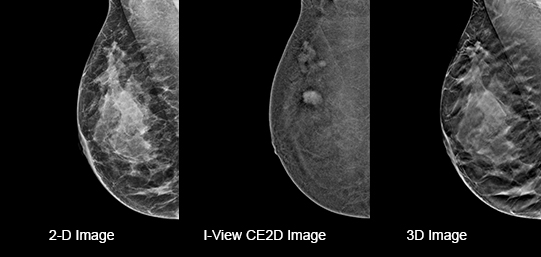

Eliminates Structural Background

Acquire a pair of high- and low-energy images in rapid succession. This allows for regions of abnormal blood flow to be displayed by subtracting the background breast parenchyma.

Contrast-enhanced mammography enhances visualization and may uncover hidden abnormalities – a crucial factor in reducing missed and or underdiagnosed cancers.